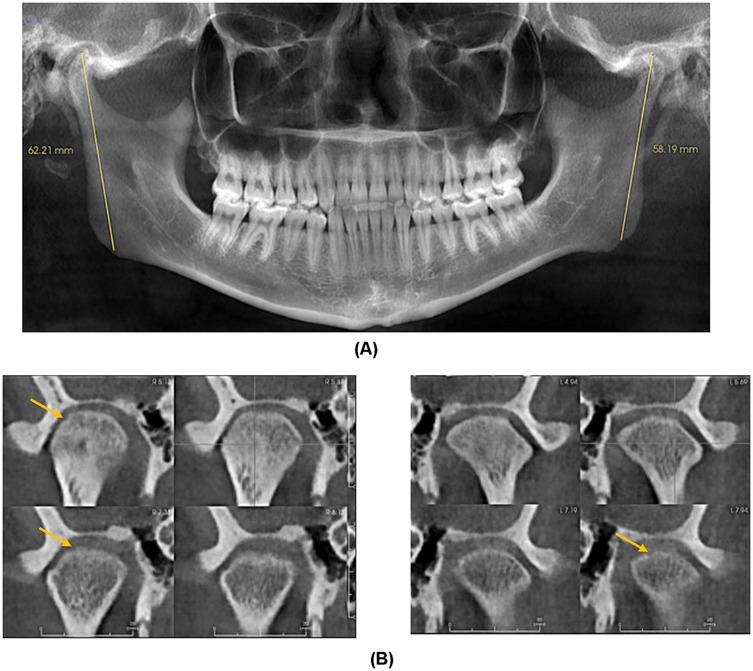

A diagnostic local anesthetic block to the R auriculotemporal nerve and R masseter trigger point resulted in the resolution of dull pain without effect on the sharp ear pain. MRI of the brain with and without contrast, with the R ear as the region of interest, revealed no intracranial or otologic pathology or cranial nerve compression or other structural abnormalities. Cone beam computed tomography (CBCT) imaging revealed mild degenerative changes in both TMJs with increased ramus height on the R side (Figure 2).

Figure 2. (A) Panoramic Image demonstrating increased right ramus height compared to left. (B) Coronal Sections of right and left condyle showing mild cortical erosion.